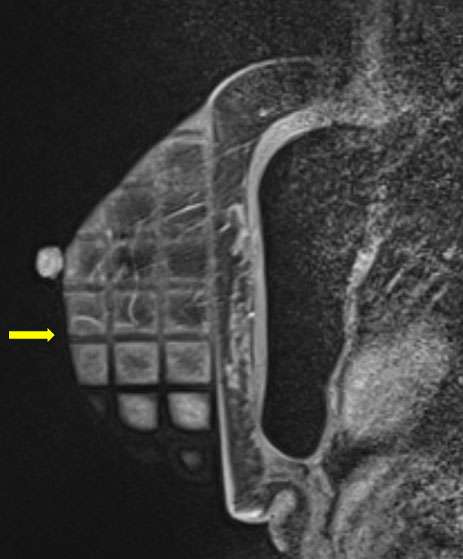

- Obtain images of the breast pre-contrast administration (fig 1) (sequences used can vary depending on institutional preferences)

Figure 1. Sagittal T1-weighted fat saturated pre contrast images demonstrate a biopsy grid overlying the lateral breast in compression. In this patient with silicone implants, the implant must be excluded during compression.